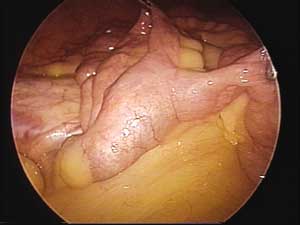

Procedeu-se o inventário do intestino delgado, no sentido retrógrado a partir da válvula

íleo-cecal, identificando-se a cerca de 60 cm

desta, formação diverticular alongada compatível

com divertículo de Meckel (Figura 2). Realizamos

| Figura 2 _ Divertículo de Meckel: aspecto laparoscópico. | Figura 3 _ Aspecto laparoscópico após a ressecção. |